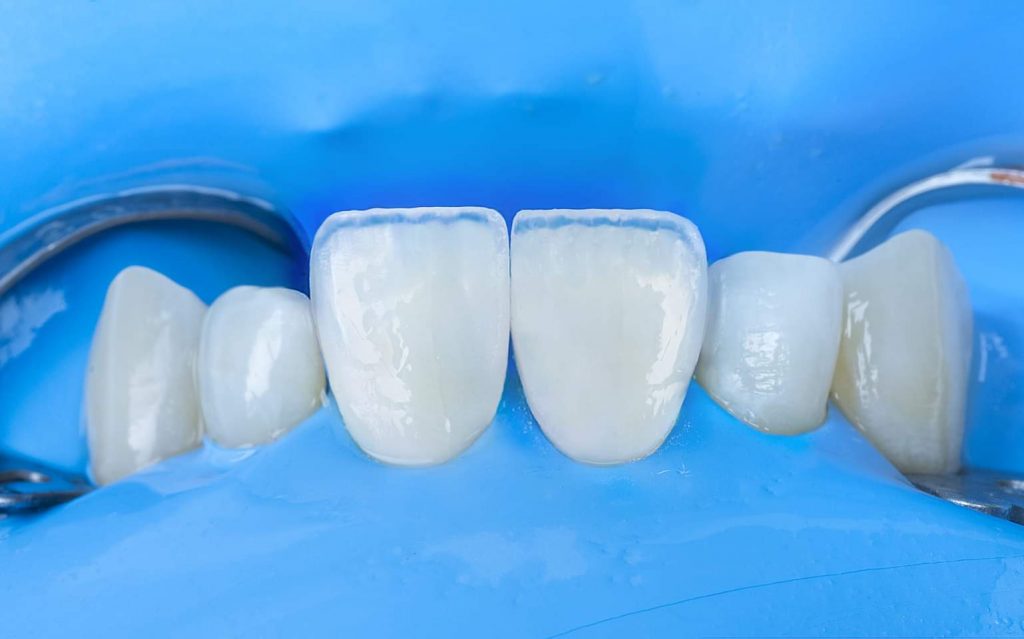

3. Step-by-step clinical procedure

The clinical treatment steps are presented in the images below, with a simple description below each image.

Clinical note: In this case, the wax-up was made only for the central and lateral incisors. However, during the clinical procedure, I noticed that the canines were also needed some correction by composite materials to achieve better morphological shapes, and to provide better smile curve.